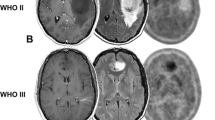

Figure 1a–c illustrates MR-PET changes in a 24-year-old female patient with a residual survival of around 1 year after the 2nd PET scan. This patient had a WHO II, IDH1 mutant, MGMT methylated diffuse glioma with multi-parametric MR-PET imaging showing increasing tumor extent crossing the midline and an increasing focus of 18F-FDOPA PET uptake over a period of about 1.3 years while on temozolomide. Conversely, Fig. 1d–f illustrates a 35-year-old male patient with a residual survival of more than 9.7 years from the 2nd PET scan. This patient had a WHO II, IDH1 mutant, unmethylated, 1p19q codeleted oligodendroglioma with a small tumor burden and minimal PET uptake that was relatively stable over 1 year of evaluation while on temozolomide.

a Fluid attenuated inversion recover (FLAIR) MRI images, b normalized 18F-FDOPA PET uptake, and c MR-PET fused images in a 24-year-old female patient with a WHO II, IDH1 mutant, MGMT methylated diffuse glioma with multi-parametric MR-PET imaging showing increasing tumor extent crossing the midline and an increasing focus of 18F-FDOPA PET uptake over a period of around 1.3 years while on temozolomide. This patient expired approximately 1 year after the 2nd PET scan. d Fluid attenuated inversion recover (FLAIR) MRI images, e normalized 18F-FDOPA PET uptake, and f MR-PET fused images in a 35-year-old male patient with a WHO II, IDH1 mutant, unmethylated, 1p19q codeleted oligodendroglioma with a small tumor burden and minimal PET uptake that is relatively stable over a year of evaluation while on temozolomide. This patient expired more than 9.7 years from the time of the last PET scan